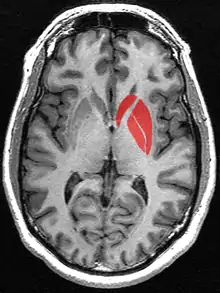

Human brain frontal (coronal) section Horizontal slice of MRI-image showing the putamen. The other nuclei of the basal ganglia (caudate nucleus and globus pallidus) can be seen as well.

Horizontal slice of MRI-image showing the putamen. The other nuclei of the basal ganglia (caudate nucleus and globus pallidus) can be seen as well. Putamen